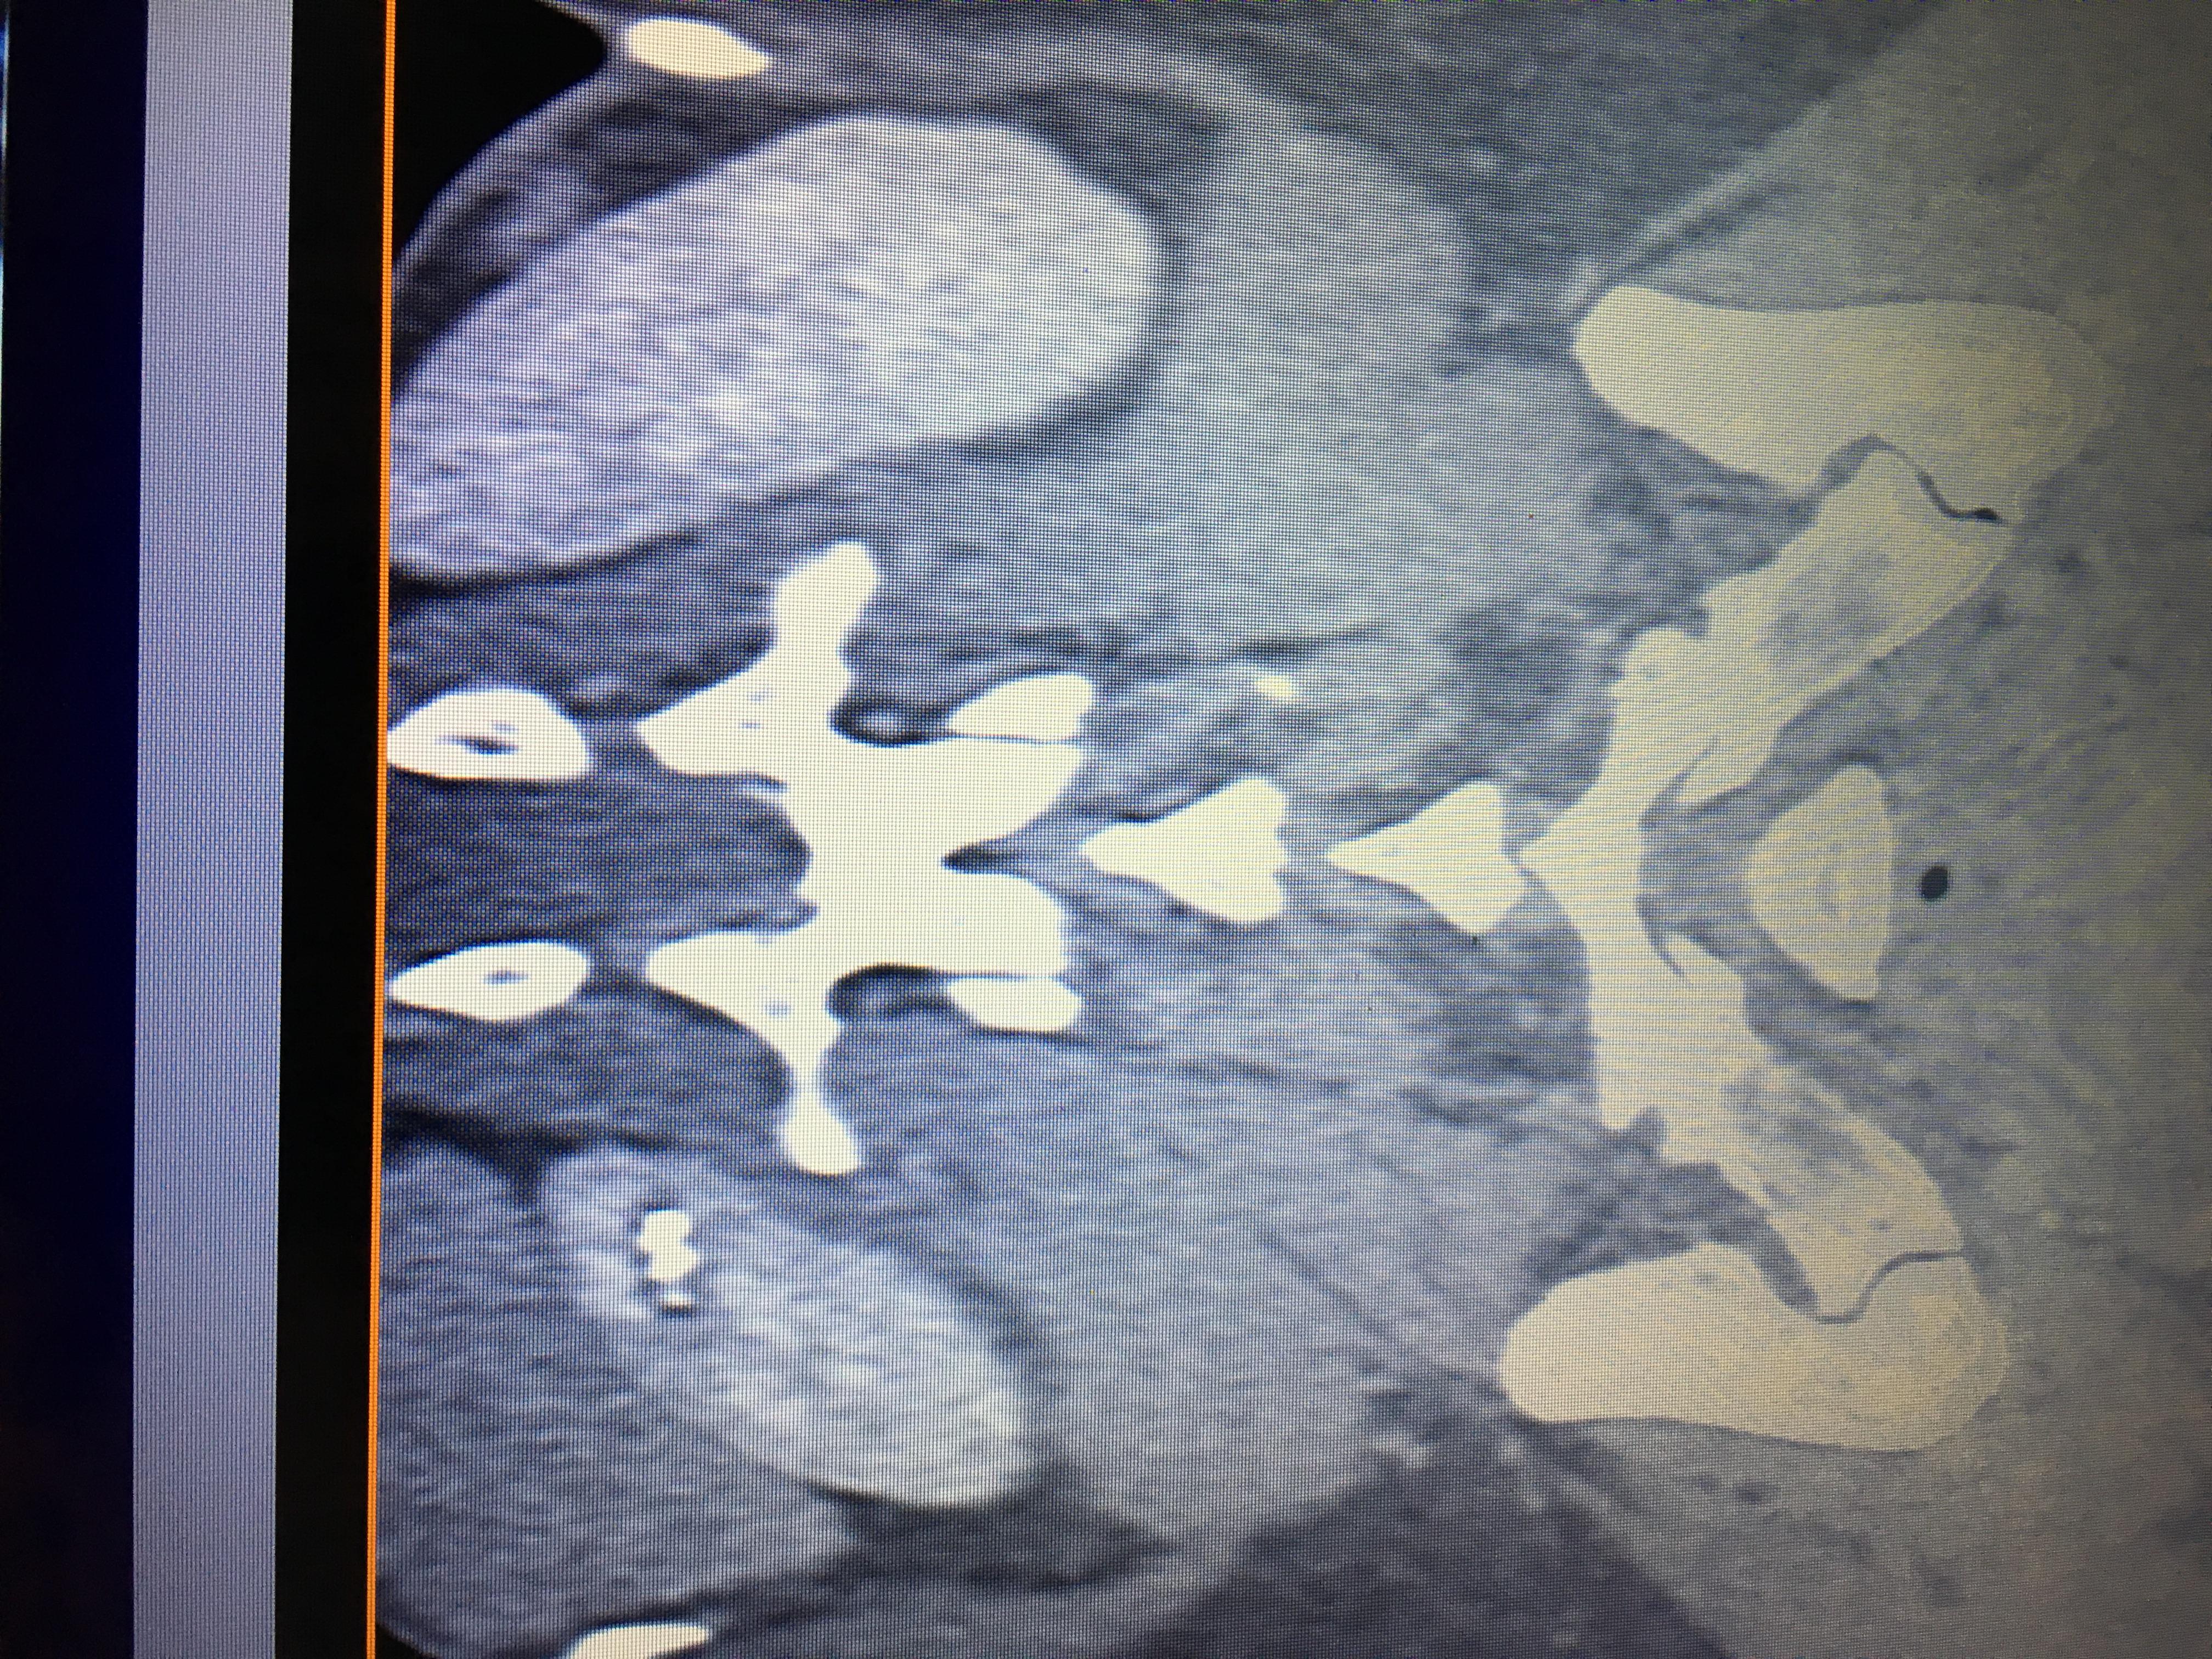

Здравствуйте,помогите, пожалуйста, с расшифровкой кт почек с контрастом. Насколько я поняла, в левой почке маленький камешек. А что за образование в правой почке? Киста с кальцинированной стенкой или камень? Спасибо за ответ!

Здравствуйте! На последнем снимке - больше данных за конкремент. Но при описании снимков должны определяться плотность образования, и нет изображения ни одного фрагмента ни одного из мочеточников. И самих снимков обычно бывает больше. Недостаточно данных для заключения.